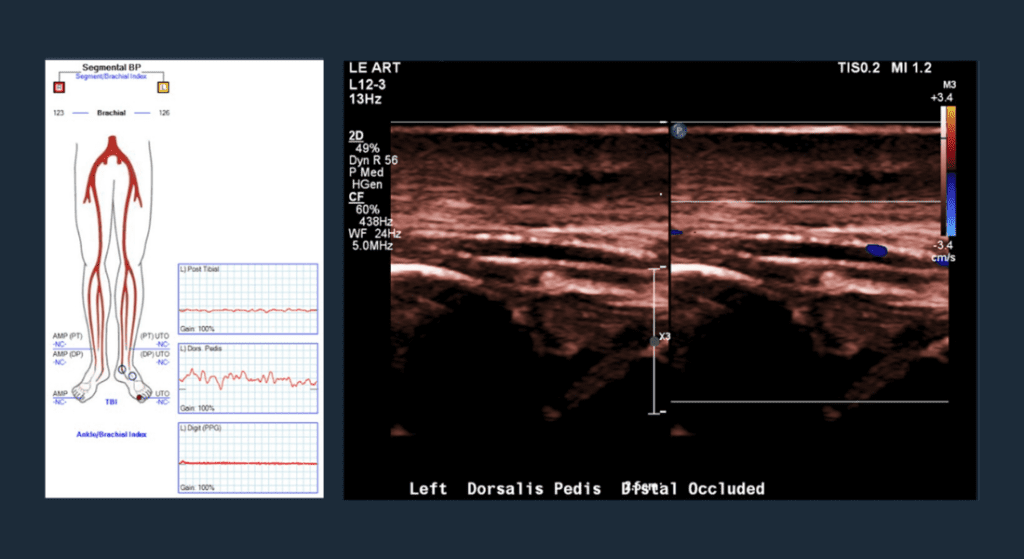

Pre-op Vascular Lab Testing

No great toe pressure; dorsal pedal occlusion.